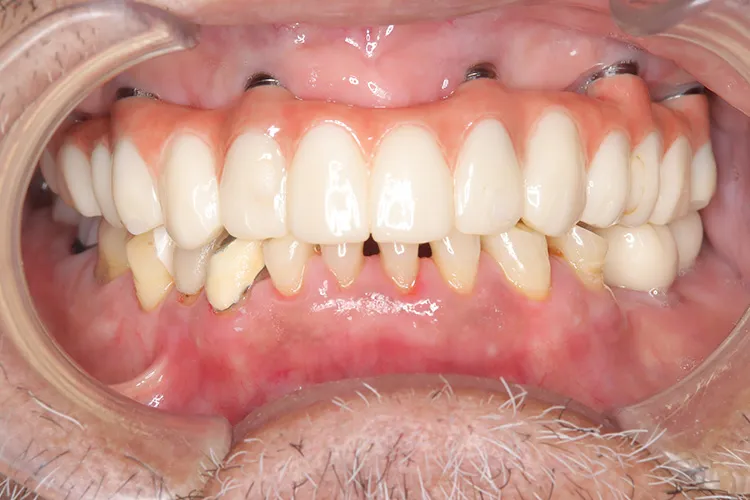

症例8/

下顎ボーンアンカードブリッジ

- 治療期間

- 6ヶ月

- 費用

- 265万円(税込)

治療前

治療後

レントゲン画像

治療内容

ボーンアンカードブリッジの下顎症例です。同じようにインプラント6本で上部構造を支えることができます。